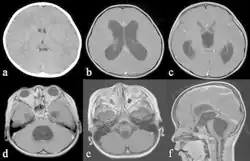

| Hydrocephalus in a three year old male patient on MRI. | |

Macewen's sign or Macewen sign (/məˈkjuːən/ mə-KEW-ən) is a sign used to help to diagnose hydrocephalus[1] (accumulation of excess cerebrospinal fluid) and brain abscesses. Tapping (percussion) the skull near the junction of the frontal, temporal, and parietal bones will produce cracked pot sound. Positive test is indication of separated sutures. This is due to raised intracranial tension.